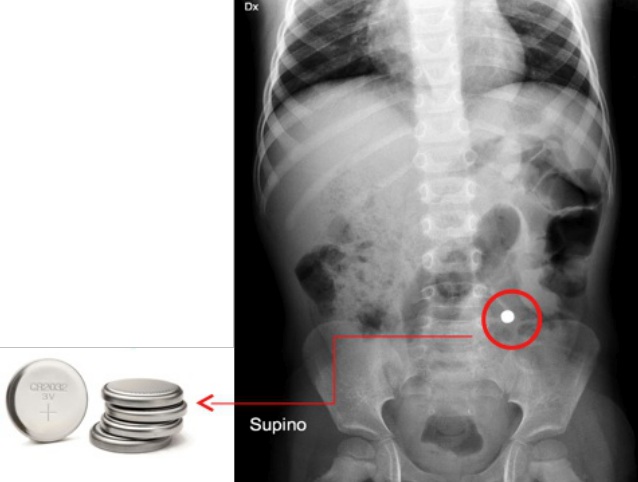

In questa occasione viene eseguita una Rx addominale in proiezione antero-posteriore che rivela la presenza di un corpo estraneo radio-opaco in sede digiuno-ileale (Figura 1).

Figura 1. Rx addominale in proiezione antero-posteriore che rivela la presenza di un corpo estraneo radio opaco in sede digiuno-ileale.

L�oggetto per forma e dimensione risultava compatibile con una disk battery e avendo questo oltrepassato il piloro, intraprendiamo (come da linee guida) un trattamento con lassativi e clisteri in modo da far espellere l�oggetto al bambino nel minor tempo possibile.